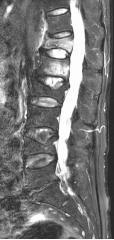

70岁的梁奶奶,家人说老人家因提重物导致腰背疼痛,正因疫情期间,在家休息仍无缓解,因疼痛无法正常生活,迫于为梁奶奶解除痛苦,居家7天后家人带其来到我院就诊,张昊主任医师阅读了相关影像学资料,经过团队的讨论,首先明确诊断为 “1.胸12、腰1椎体压缩性骨折 2.重度骨质疏松症”。针对老年人骨质疏松导致椎体压缩性骨折的治疗,把相关治疗方案以及相应的风险等事宜详细告知家属,最终采用经皮穿刺椎体后凸成形术为梁奶奶进行手术,术后疼痛明显缓解,效果非常满意,第二天顺利出院。

术前影像